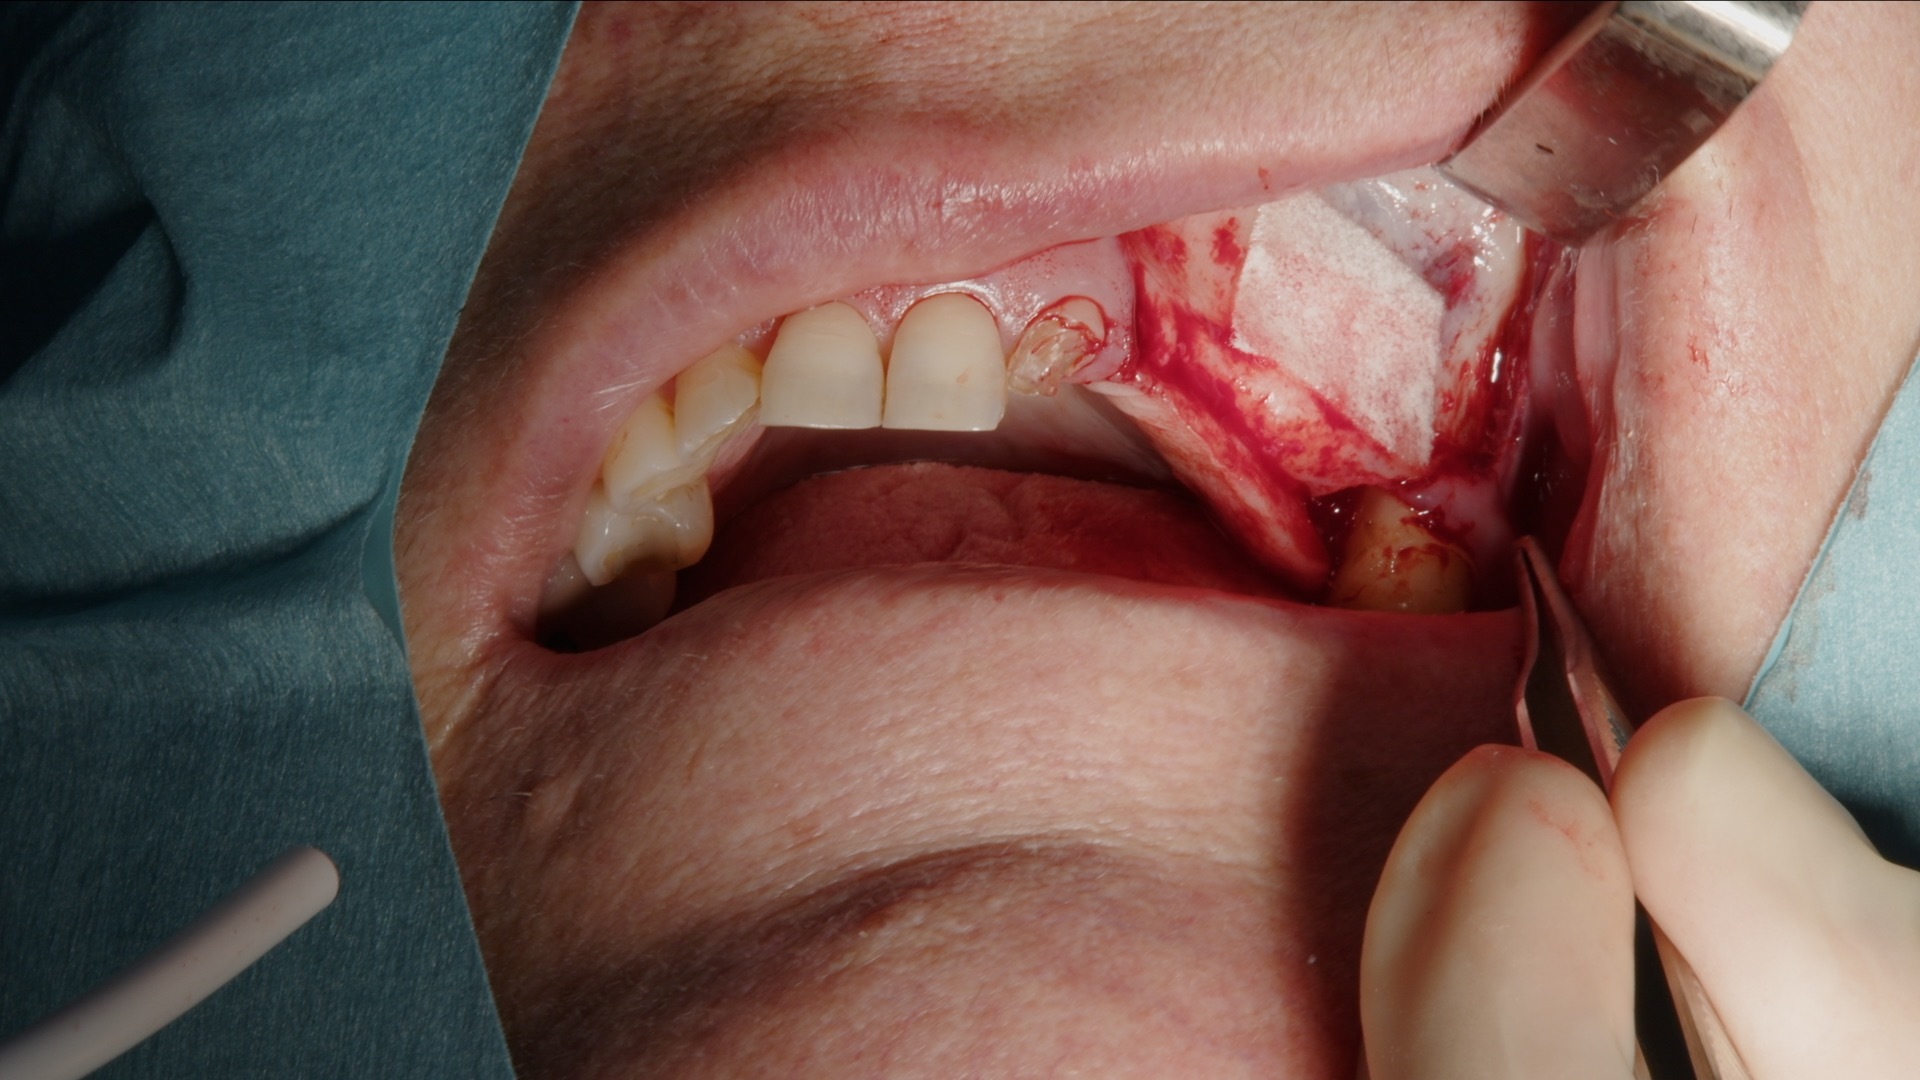

3. Skonsam elevation av sinusmembranet med piezo-lyftspets.

4. Fullt preparerat lateralt fönster inför augmentation.

5. Ifyllnad med blandning av Geistlich Bio-Oss och autologt ben.